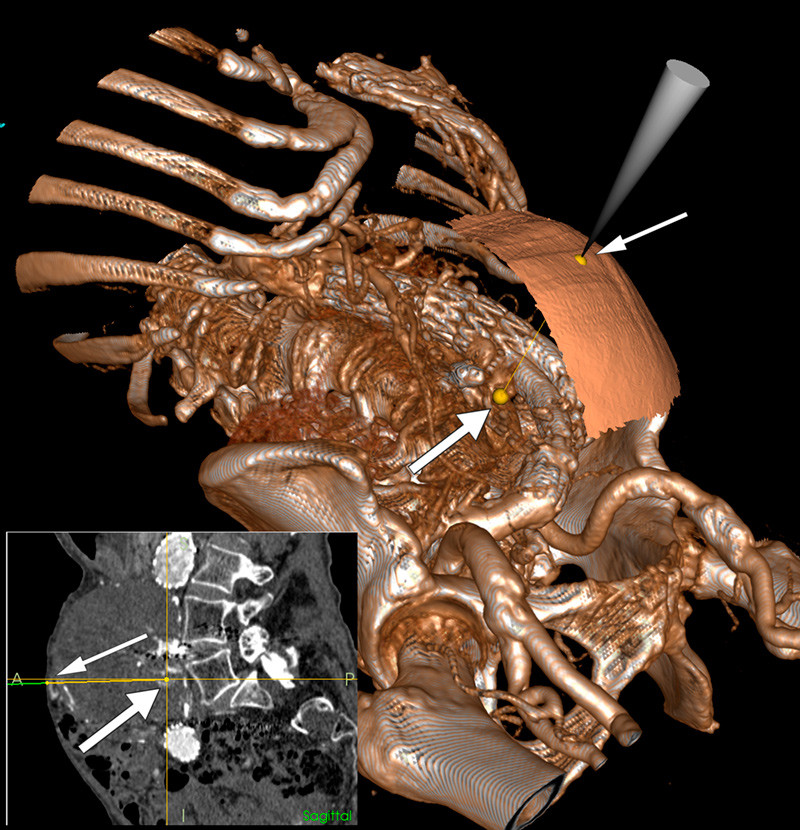

In a female patient given a stent-graft repair to treat an abdominal aortic aneurysm, a retrograde blood flow arose via collateral vessels through two lumbar arteries and in between the aortic wall and the stent graft. CT scans showed the aneurysm enlarging, with constant risk of rupture. Attempts at endovascular embolisation of the blood vessels, which normally supply the network of collateral vessels, were unsuccessful. Anattempt was therefore made to embolise the vessels directly using a microcatheter through a percutaneously inserted needle with the needle point close to the lumbar arteries. The needle placement is normally CT-guided, but that involves transferring the patient to an angiography suite where the actual embolisation is performed, and it is not possible to reposition the needle.

The Norwegian National Competence Centre for Ultrasound and Image-Guided Therapy has developed a navigation system (1) that continuously shows the position of different instruments in a three-dimensional image. In an angiography suite with integral 3D imaging equipment it was possible using this navigation system to perform percutaneous embolisation without having to move the patient. The large image is a 3D image of the patient with the needle point placement on the surface of the skin (thin arrow) and directed towards one of the lumbar arteries (thick arrow). This method permits the needle to be placed to optimum effect and its position monitored throughout the procedure with the possibility for multiple insertions based on the same CT-image acquisition. The small image is that of the same setup in the sagittal plane. The microcatheter was introduced via the needle, and the lumbar arteries embolised with Onyx injections. A check-up eighteen months later showed no leak and the size of the aneurysm was unchanged. The method is experimental and is part of an ongoing research project.